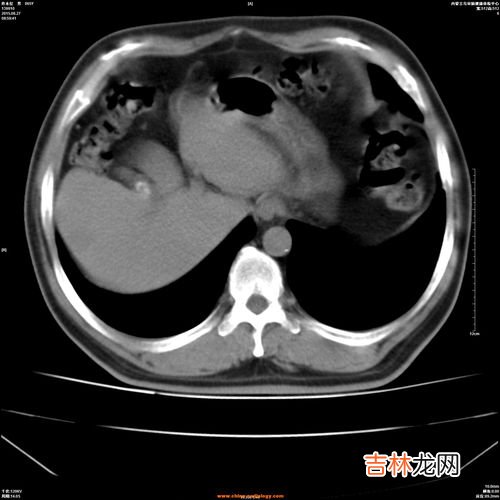

文章插图